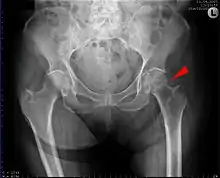

Intertrochanteric hip fracture in a 17-year-old male | |

A hip fracture is a break that occurs in the upper part of the femur (thigh bone), at the femoral neck or (rarely) the femoral head.[2] Symptoms may include pain around the hip, particularly with movement, and shortening of the leg.[2] Usually the person cannot walk.[3]

A hip fracture is usually a femoral neck fracture. Such fractures most often occur as a result of a fall.[3] (Femoral head fractures are a rare kind of hip fracture that may also be the result of a fall but are more commonly caused by more violent incidents such as traffic accidents.) Risk factors include osteoporosis, taking many medications, alcohol use, and metastatic cancer.[2][1] Diagnosis is generally by X-rays.[2] Magnetic resonance imaging, a CT scan, or a bone scan may occasionally be required to make the diagnosis.[3][2]